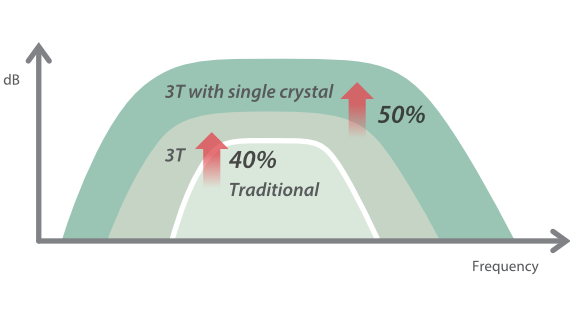

Transdutores